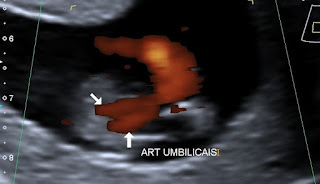

| Figura 3 - Ultrassonografia mostrando artéria umbilical única passando em volta da bexiga fetal no 1º trimestre. |